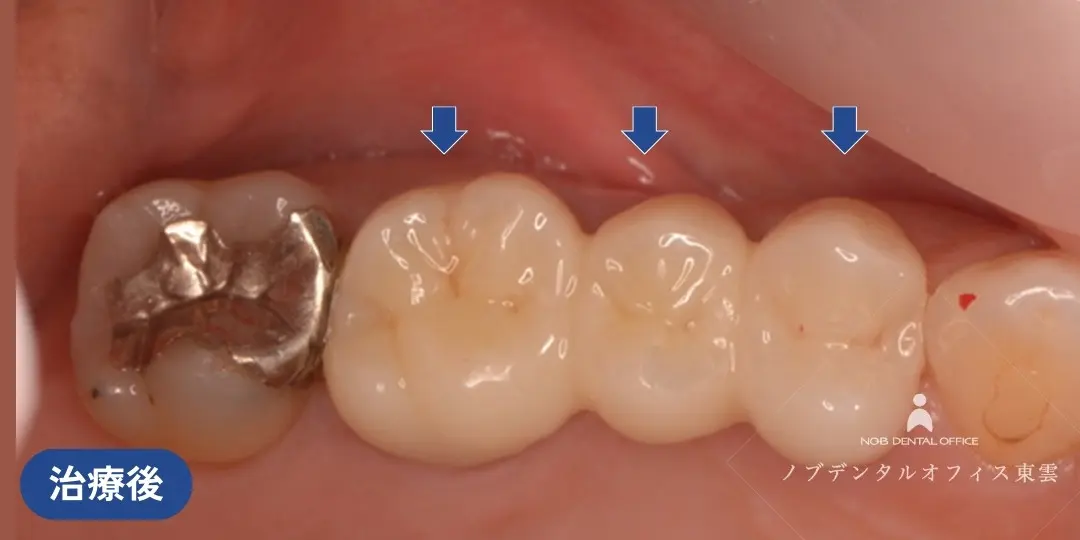

ブリッジの再治療をジルコニアで行った症例(40代女性)

右上の奥歯にすでに保険適用の金属のブリッジが入っていました。

| 治療 | ・根管治療の再治療 ・歯周外科処置(歯ぐきの形態修正) ・ジルコニアブリッジ |

| 費用 | かぶせ物の費用:143,000円×3本 保険適用 |

| リスク | ・経年的に摩耗が起こることがあります。 ・強い噛みしめや歯ぎしりにより、欠けたり外れる可能性があります。 ・歯ぐきの状態によっては境目が見えてくる場合があります。 ・清掃状態や生活習慣によっては境目から虫歯や歯周病が起こることがあります。 |